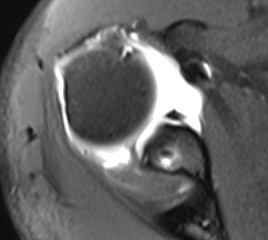

Case 2

Recurrent instability

- non recognised bony defect

- revised with Latarjet